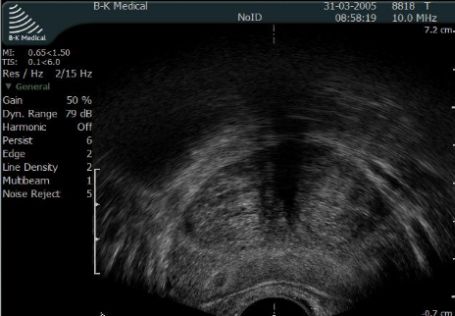

Diagnostyka podwyższonego poziomu PSA polega na wykonaniu na biopsji gruczołu krokowego czyli pobraniu wycinków do badania histopatologicznego. Badanie wykonywane jest pod kontrolą USG - do tego celu wykorzystywana jest głowica transrektalna.

Fot. Obaraz gruczołu krokowego w czasie transrektalnego USG - TRUS.

W czasie biopsji pobieranych jest od kilku do kilkunastu wycinków - ilość zależna jest od stężenia PSA, wieku pacjenta i standardu obowiązującego w danym ośrodku. Biopsja gruczołu krokowego jest standardowym badaniem wykonywanym na wszystkich oddziałach urologicznych w ramach NFZ. Więcej informacji na temat biopsji stercza znajdzie Pan w artykule: Biopsja gruczołu krokowego pod kontrolą USG.